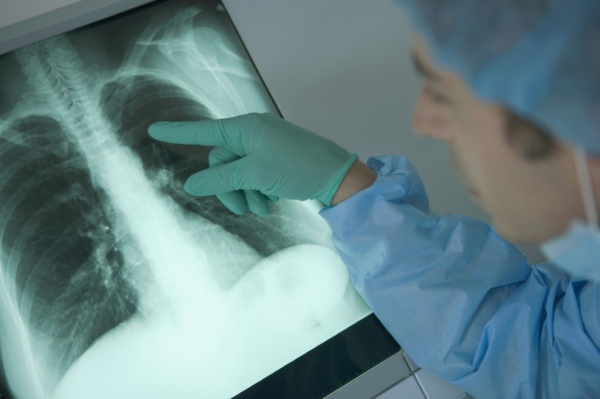

Лечение гемангиом грудной клетки может включать гормональную терапию и аппаратные манипуляции.

Перед удалением гемангиом на грудной клетке определяют ее тип, что позволяет предупредить распространение патологичных клеток в ткани и органы. Нахождение гемангиом в органах грудной области может нарушать их функции. Метод удаления определяет врач, исходя из вида, глубины поражения, объема, размера образования. Не рекомендуется использовать народные методы лечения заболевания, потому как при неправильном применении происходит ухудшение клинической картины или стимуляция роста и развития опухоли. Гемангиома в большинстве случаев носит доброкачественный характер и не угрожает здоровью.